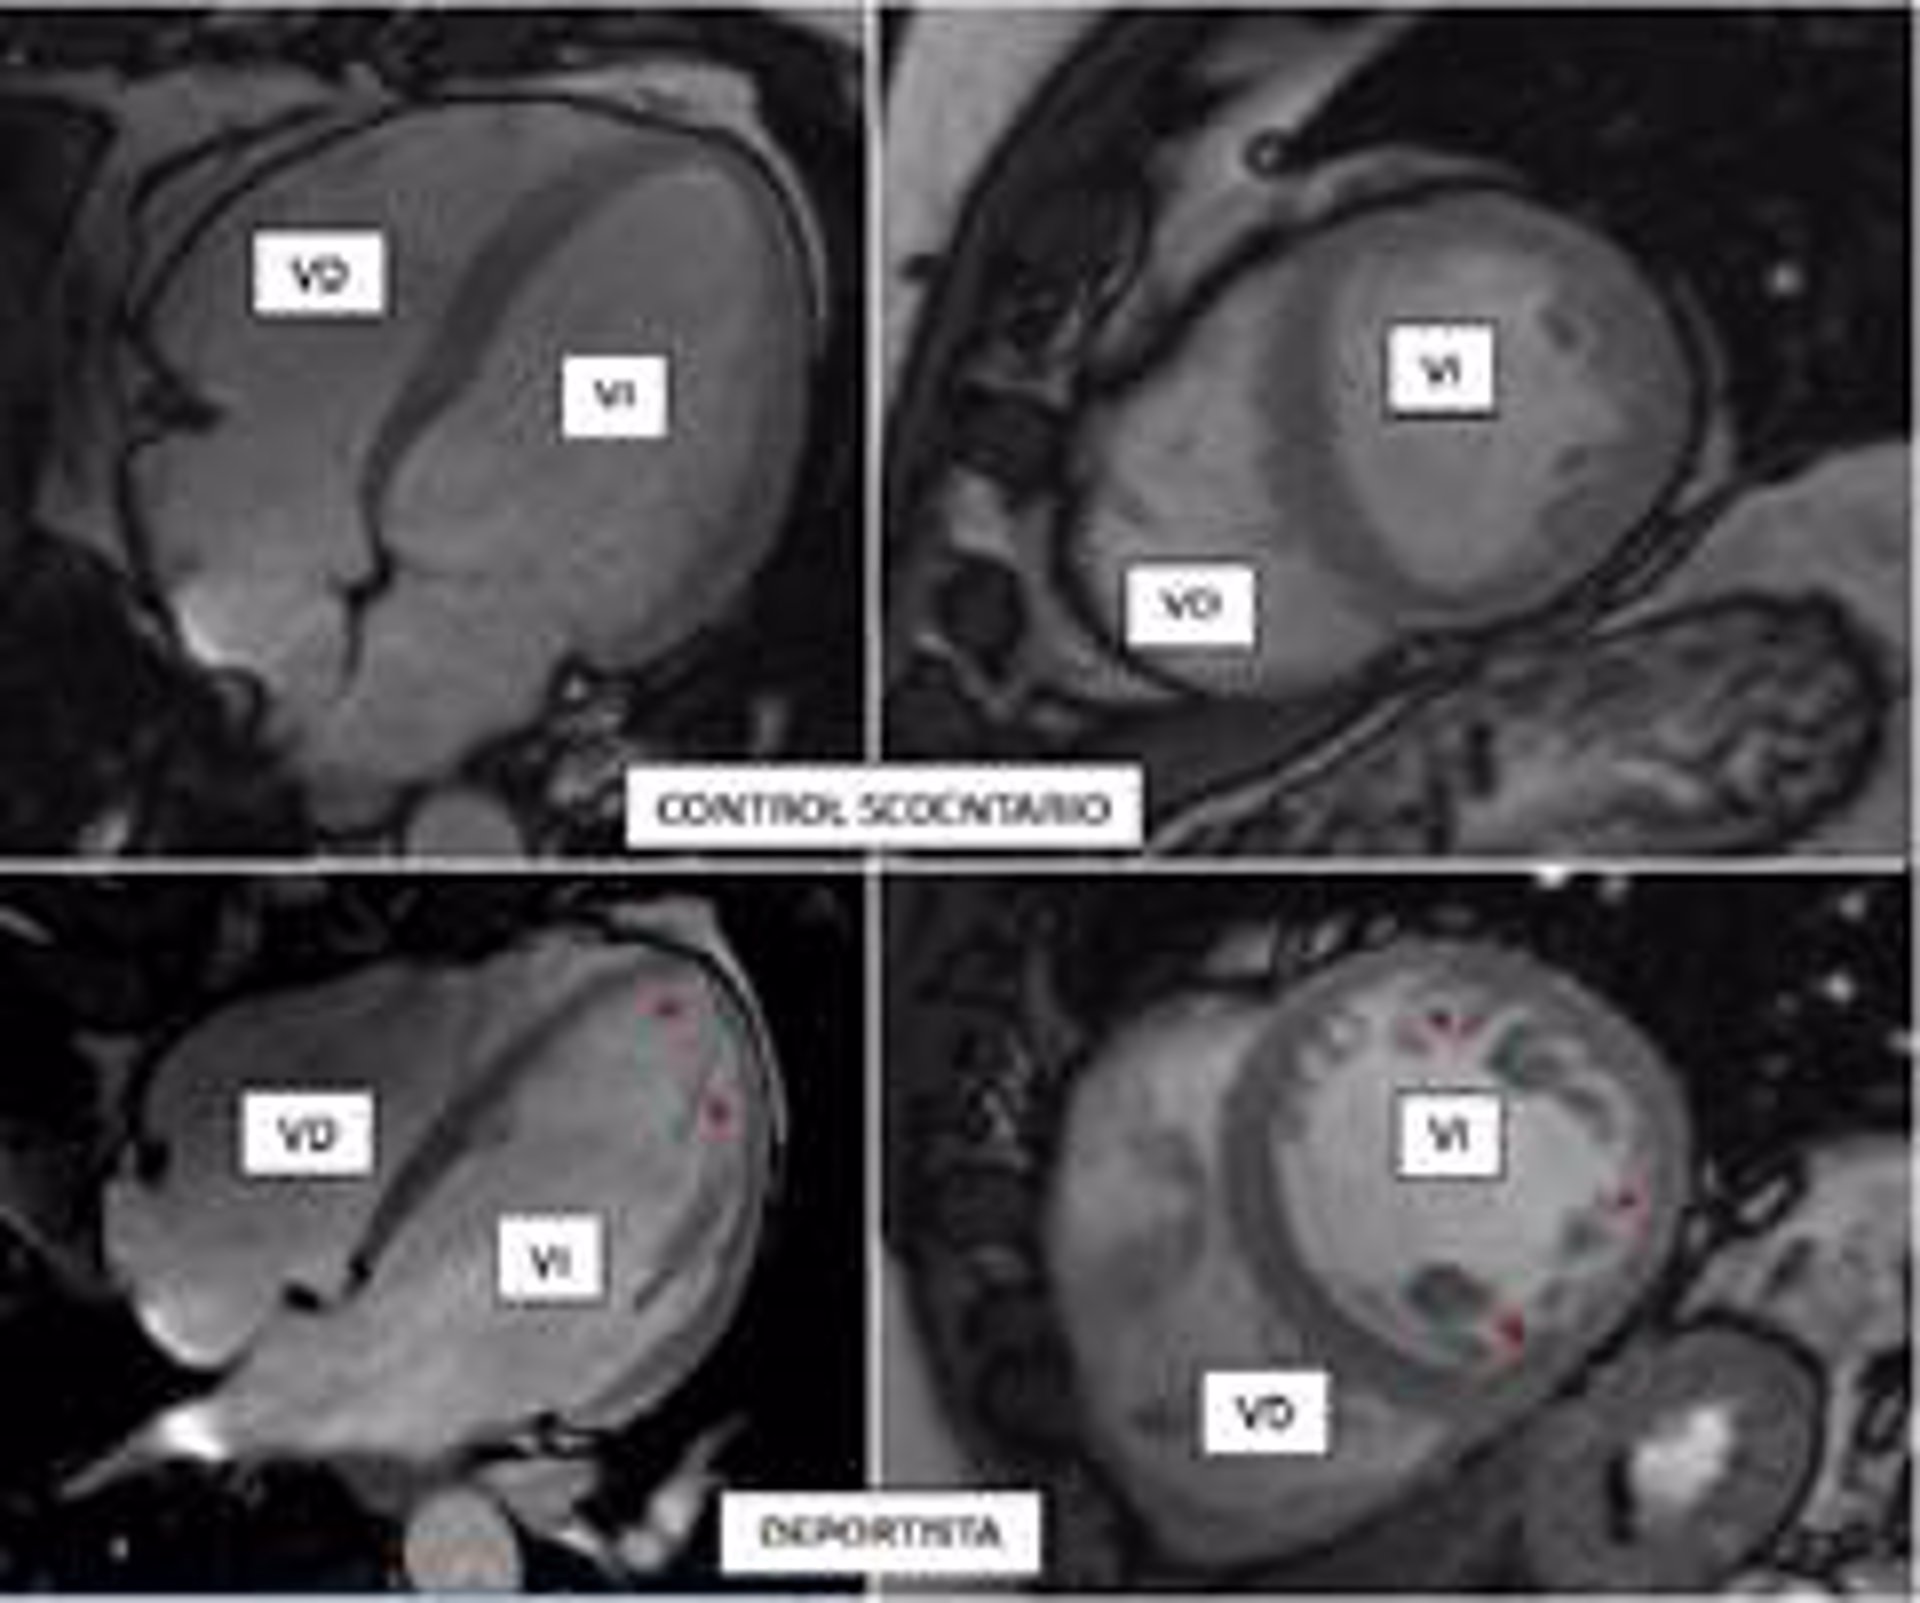

MURCIA (E.P.). Investigadores del Centro Nacional de Investigaciones Cardiovasculares (CNIC) han demostrado que el ejercicio físico vigoroso se asocia a una "descompactación" del corazón, que adopta una morfología esponjosa.

La práctica de ejercicio, intenso o moderado, es una de las recomendaciones de salud aceptadas por todos los expertos. Sin embargo, el entrenamiento de alta intensidad puede desencadenar una serie de cambios fisiológicos en el organismo, incluyendo el corazón. Por ejemplo, se sabe que los deportistas presentan una adaptación de su corazón al entrenamiento que, entre otros fenómenos, puede incluir un aumento de las trabéculas en su interior ("hipertrabeculación"), que es benigna pero que puede confundirse con una patología genética hereditaria, la miocardiopatía no compactada, que puede causar muerte súbita.

En la miocardiopatía no compactada, las paredes del corazón se adelgazan y el músculo cardiaco, habitualmente compacto, se sustituye por una porción esponjosa (trabeculada), que se comunica directamente con el interior de los ventrículos.

El trabajo ha evaluado mediante resonancia magnética cardiaca la presencia de criterios reconocidos de miocardiopatía no compactada en más de 700 participantes del estudio 'PESA-CNIC-SANTANDER', trabajadores sanos del Banco de Santander que realizan diferentes grados de actividad física, pero que no practican deporte de forma profesional.

Lo primero que se observó es que el músculo cardiaco de los participantes, que de forma persistente realizaron una actividad física vigorosa a lo largo de este periodo de tiempo, se adaptaba al ejercicio aumentando su volumen y su masa muscular. "Estos cambios son conocidos como 'corazón de atleta', y se consideran fisiológicos", explica García-Lunar.

Un hallazgo más novedoso fue que una tercera parte de los individuos (hombres y mujeres) con un nivel elevado de actividad física vigorosa habitual cumplía además los criterios diagnósticos de miocardiopatía no compactada, pero, obviamente, no estaban enfermos.